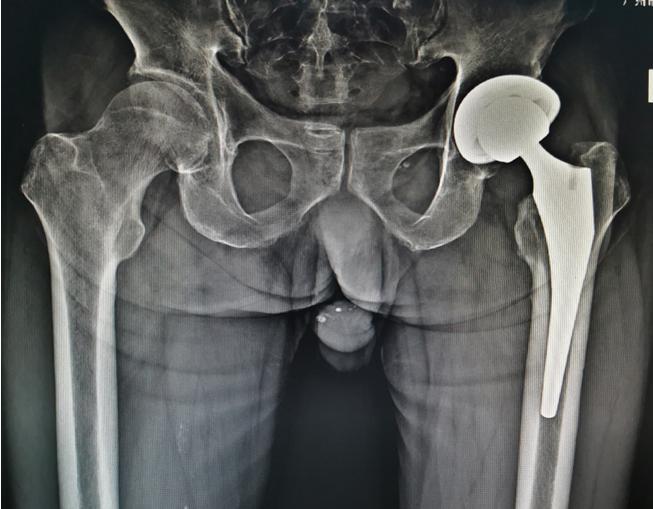

股骨颈骨折术前

股骨颈骨折术后